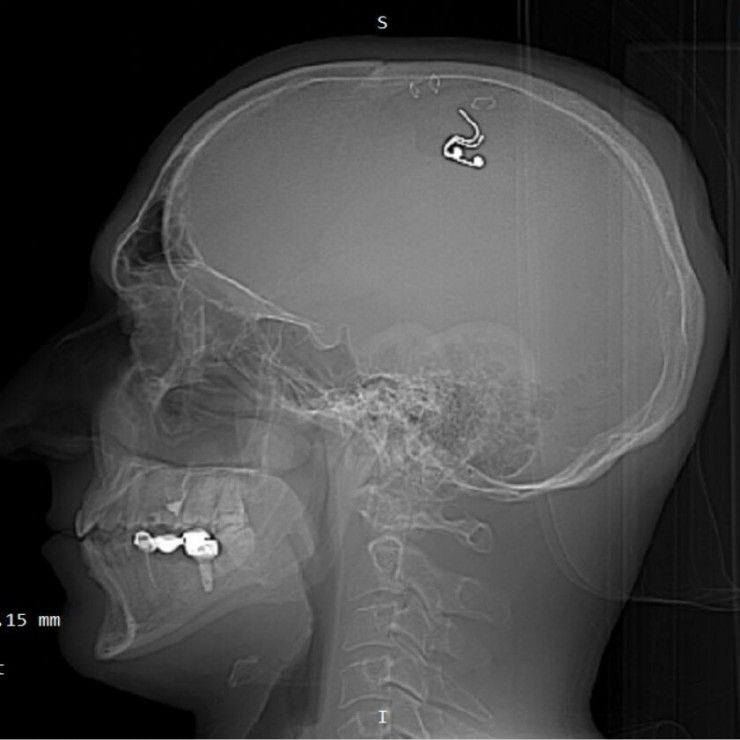

В качестве доказательства проведения операции у Михаила есть несколько фотографий с оттянутой скобами кожей на голове и вставленным в отверстие электродом, а также фото, где он в запачканной в крови майке сидит с приставленной к затылку дрелью. Также, по словам мужчины, у него есть четырехчасовое видео операции.

Фото Twitter/Michael Raduga